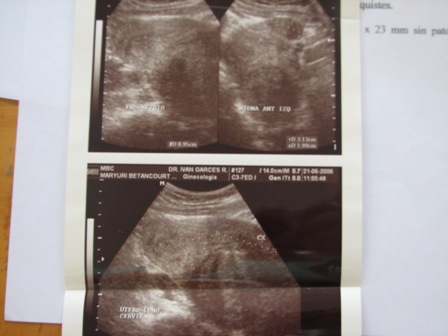

Maryuri had an ultrasound performed a year or so earlier. It actually demonstrates the correct anatomy of the location of the fibroids.